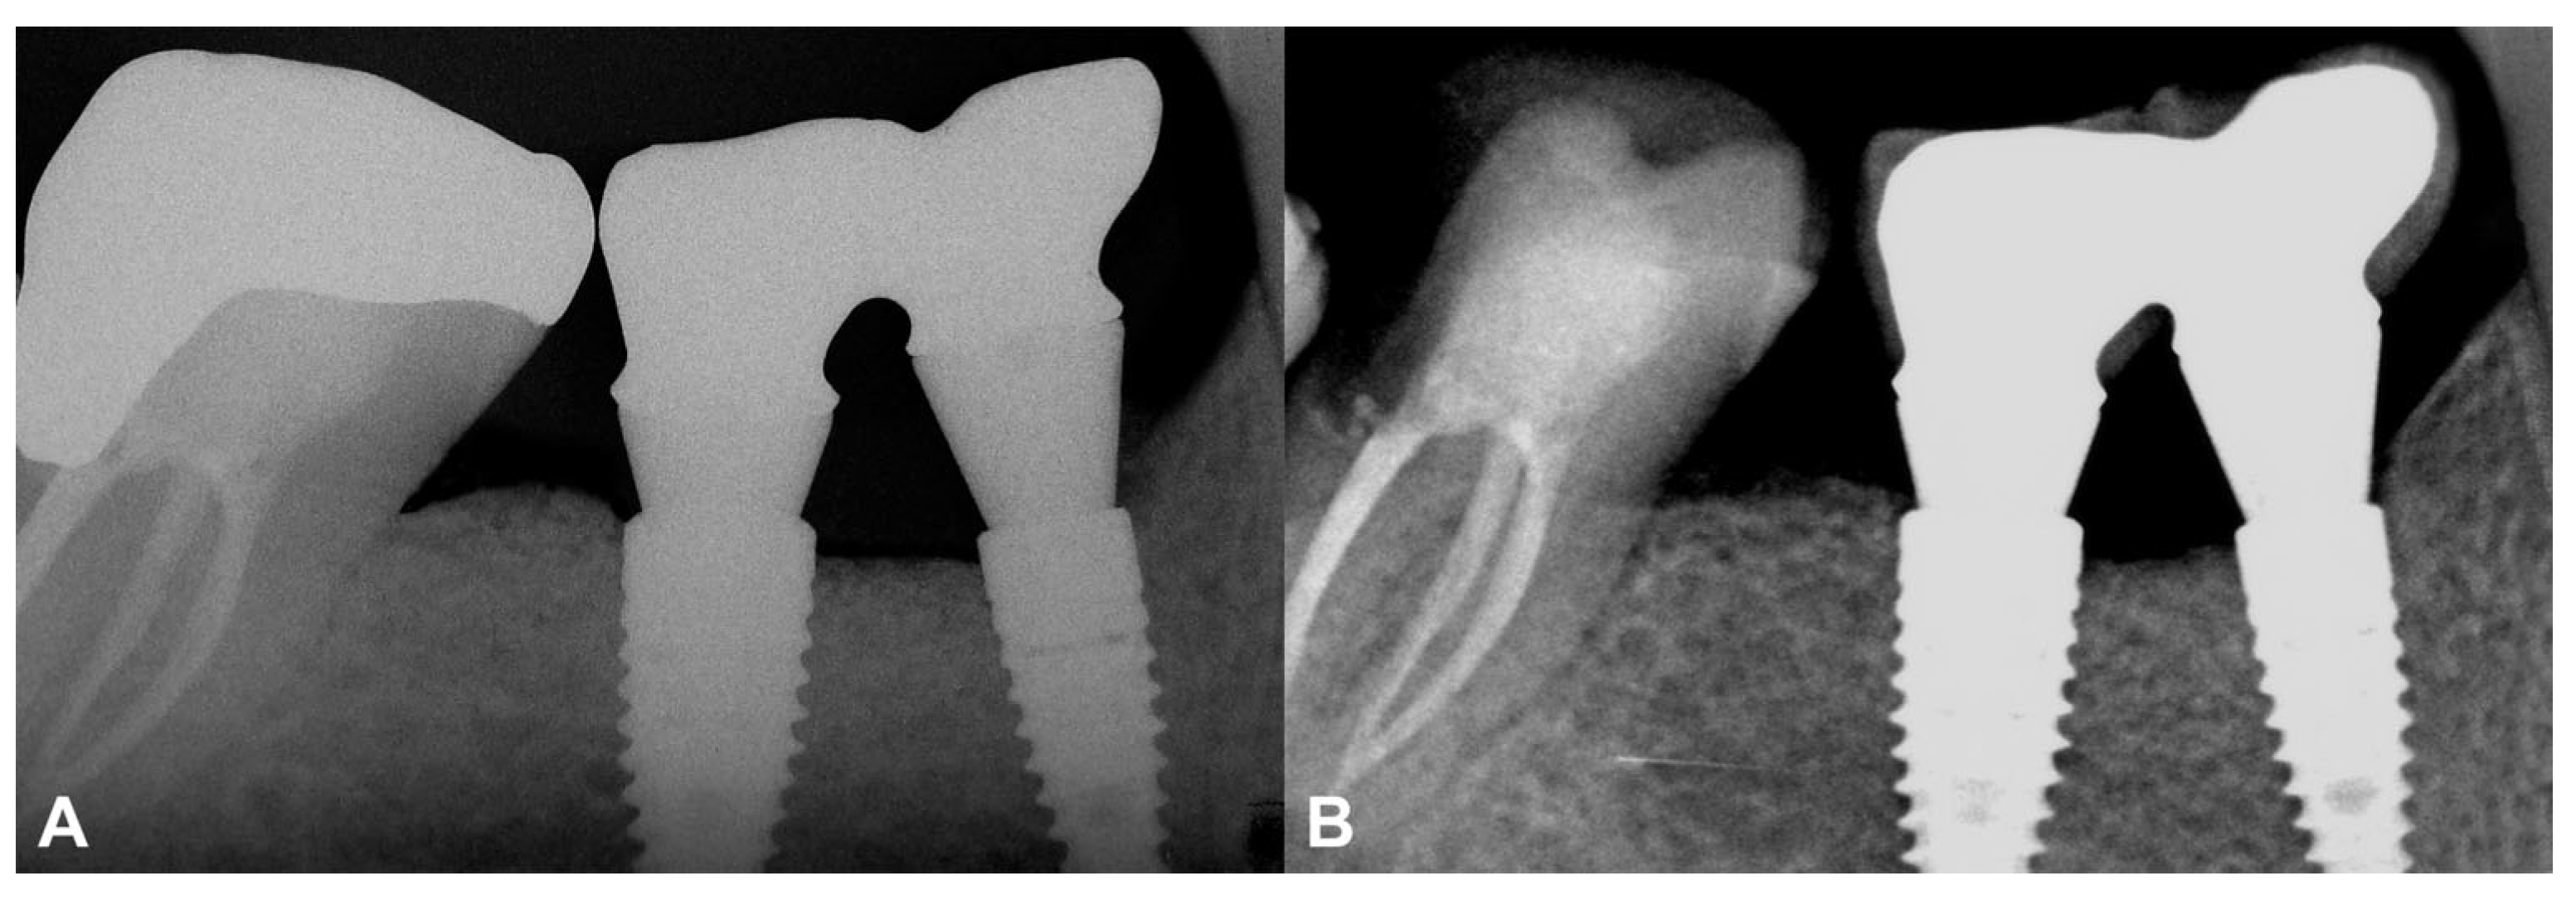

3.2. Case #2

3.2.1. Baseline Clinical Situation

3.2.2. Short-Term Volumetric Hard Tissue Gain and Long-Term Follow-Up